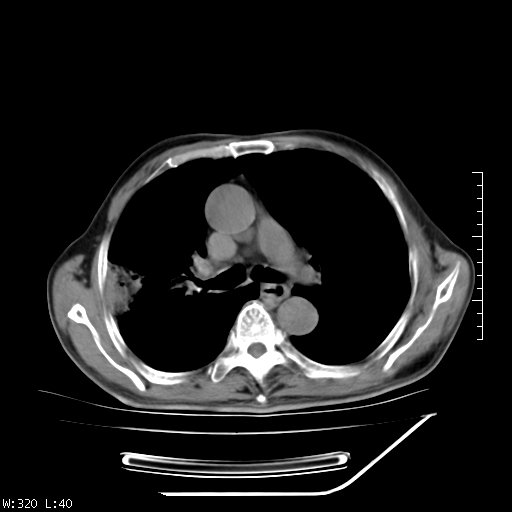

标题: CT23994:男、72、咳嗽、气短两月余,近来消瘦。 [打印本页]

标题: CT23994:男、72、咳嗽、气短两月余,近来消瘦。

右上肺实变,与胸膜关系密切,右肺容积缩小,隆突下淋巴结增大,考虑1 肺结核 2 肺癌

右上肺大片状密度增高影,与胸膜关系密切,内见低密度透亮影,胸膜下可见三角形不张影,左下肺沿支气管走形结节影,纵膈内淋巴结显示。考虑结核并疤痕性不张可能性大,建议穿刺活检,排除肺泡癌。

以下是引用muzi888在2010-1-6 9:43:00的发言:[br]右上肺实变,与胸膜关系密切,右肺容积缩小,隆突下淋巴结增大,考虑1 肺结核 2 肺癌